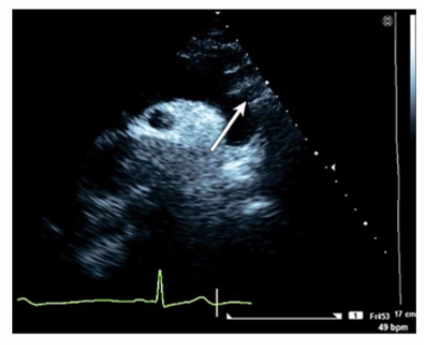

Which artery is identified by the arrow on this image?

The image is a suprasternal or high parasternal echocardiographic view of the aortic arch and its branches. The arrow points to the first large branch arising from the aortic arch, which is the brachiocephalic artery (also called the innominate artery). This vessel courses superiorly and bifurcates into the right common carotid and right subclavian arteries.

The left common carotid artery is the second branch from the arch, the left subclavian artery is the third branch, and the right common carotid is a branch of the brachiocephalic artery, not directly off the arch.

This anatomic arrangement and its echocardiographic depiction are well documented in adult echocardiography references and vascular ultrasound guidelines12:ASE Vascular Imaging Guidelinesp.270-27516:Textbook of Clinical Echocardiography, 6ep.400-405.